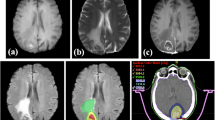

Segmentation procedure

Segmentation was performed using an in-house semi-automatic segmentation procedure26,28. Tumors were automatically delineated by using a gray-level threshold chosen to identify the largest contrast-enhancing tumoral volume. Then, a biomedical engineer/applied mathematician (B. O.-T.) carefully corrected each segmentation, slice by slice, using a brushing/pixel-removing tool. The segmentation process is summarized in Fig. 1. The outcome was cross-checked by three researchers with more than seven years of expertise on MRI (D. M.-G., J. P.-B., V. M. P.-G.) and then corrected by one of the radiologists participating in the study (B.A, A.O.M, D.A, L.A.P.-R., E.A.). The raw medical images in DICOM format were used in this procedure, so they were not modified to perform the tumor segmentations.